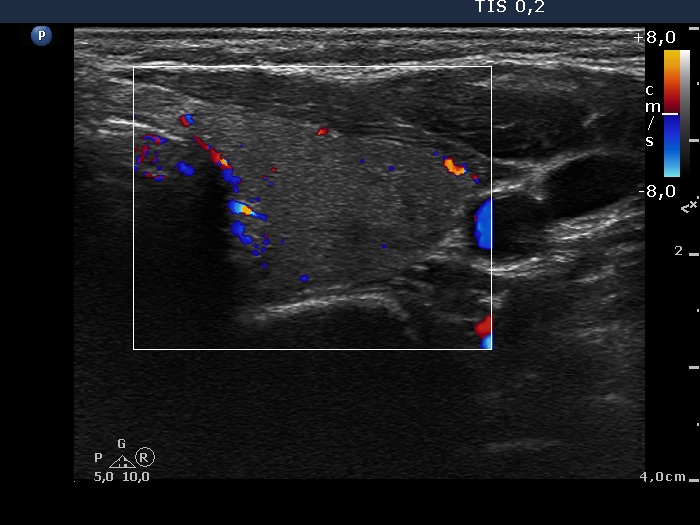

Subacute granulomatous thyroiditis - case 1777

Five months after the first examination (ultrasonographic picture 8)

Left lobe, transverse scan, color Doppler mode. The vascularization is decreased.